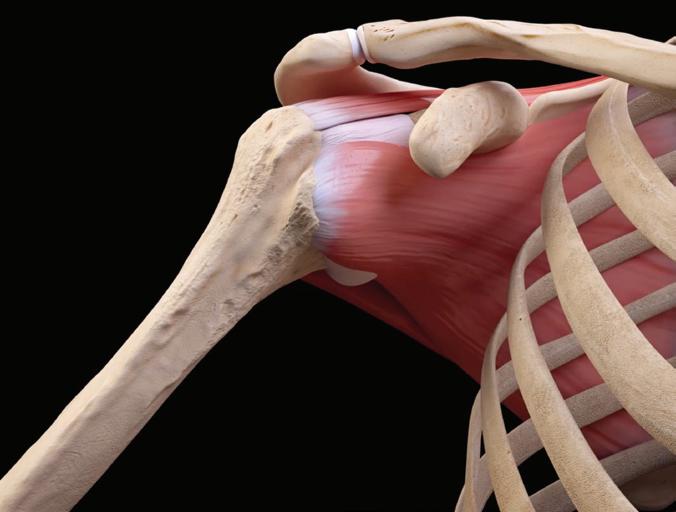

Your Trusted Resource for Orthopedic Knowledge

OrthoPedia, an open-access website, offers a comprehensive online library of peer-reviewed educational videos designed for professionals and students in musculoskeletal medicine. Watch for monthly content updates!

Anatomy

Based on pathology

Biomechanics

Pathomechanics and classifications

OrthoPedia is just one of the innovative tools that Arthrex has developed and uses to fulfill our core value of Making People Better.

Clinical Applications

Surgical procedures by experts

© Arthrex GmbH, 2021. All rights reserved. AD2-000330-en-US_A

For more information, visit OrthoPedia.com